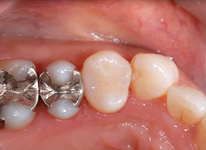

セラミックインレー

昔詰めた銀歯のお色が気になる方や金属アレルギーが心配な方へ

透明で美しく変色しにくい素材をおすすめします。見た目が天然歯に近い素材なので、区別がつきにくく年数がたっても変色しにくいことが特徴です。

Before

After